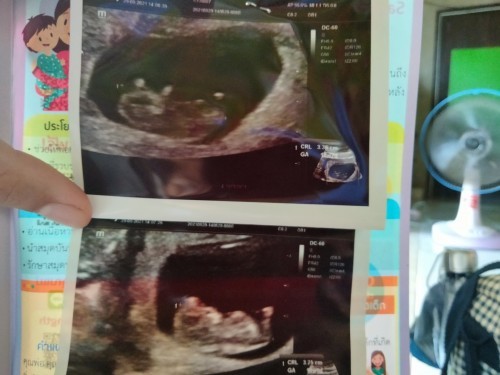

20 พฤษภาคม65 จ้า ตอนนี้13 wค่ะ คนแรกเหมือนกันค่ะ

บ้านนี้กำหนดคลอด2พฤษภา65ค่ะ 11w3